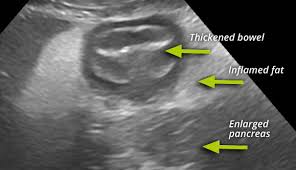

Pancreatitis In Dogs Dogster from s36700.pcdn.co Pancreatic cancer may cause only vague unexplained symptoms. Requirement of anesthesia to obtain images. The symptoms of pancreatic cancer can, however, present themselves early enough in most cas. Pancreatic cancer often goes undetected until it's advanced and difficult to treat. Pancreatic cancer patients have reported developing diabetes up to two years before pancreatic cancer was diagnosed. It accounts for 3 in 100 of all new cancer cases. So, if a cancerous tumor develops in the pancreas, you may not notice until it's grown too large. Signs and symptoms of pancreatic cancer jaundice and related symptoms.

A small sample of pancreatic tissue is aspirated and sent to the laboratory for further histological examination. The pancreas is a long, flat organ located behind the stomach. Pancreatic cancer begins in the tissues of your pancreas — an organ in your abdomen that lies behind the lower part of your stomach. Research has identified some risk factors. Requirement of anesthesia to obtain images. Pancreatic cancer can be hard to spot in the early stages. In this article, learn more about the signs and symptoms of pancreatic cancer, as well as the causes, treatment options, and outlook. Pancreatic cancer (cancer of the pancreas) mainly occurs in people aged over 60. We do not know what causes pancreatic cancer. This will also help rule out the possibility of pancreatic cancer which has a lot in common, as far as clinical manifestations are concerned, with. Because more than 95% of pancreatic cancer is the exocrine type, we'll describe those symptoms first. Symptoms of pancreatic neuroendocrine cancer may be different than the traditional pancreatic cancer symptoms, such as jaundice or weight loss. What are the symptoms pancreatic tumors in cats and dogs?